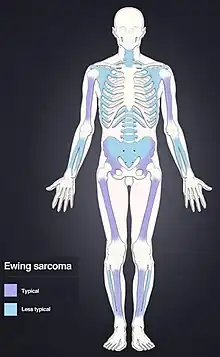

Ewing sarcoma is a type of pediatric cancer[5] that forms in bone or soft tissue.[1] Symptoms may include swelling and pain at the site of the tumor, fever, and a bone fracture.[2] The most common areas where it begins are the legs, pelvis, and chest wall.[4] In about 25% of cases, the cancer has already spread to other parts of the body at the time of diagnosis.[4] Complications may include a pleural effusion or paraplegia.[3]

Ewing sarcoma is more common in males (1.6 male:1 female) and usually presents in childhood or early adulthood, with a peak between 10 and 20 years of age. It can occur anywhere in the body but most commonly in the pelvis and proximal long tubular bones, especially around the growth plates. The diaphyses of the femur are the most common sites, followed by the tibia and the humerus. Thirty percent are overtly metastatic at presentation, while 10–15% of people present with a pathologic fracture at the time of diagnosis.[11] People usually experience extreme bone pain. Rarely, it can develop in the vagina.[12][13]